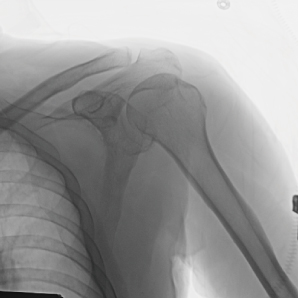

Qualité d'image supérieure avec FPD

Équipé de son détecteur à panneaux plat de 21 * 21 cm ou 30 * 30 cm, ce système produit des images claires et délicates tout en maintenant une large gamme dynamique, offrant une grande visualisation des détails avec un grand champ de vision.